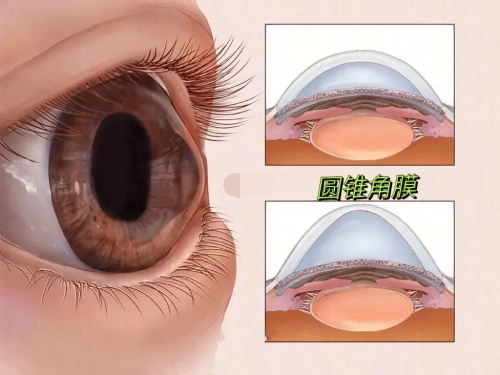

黄斑病变:老年性黄斑变性、黄斑裂孔、黄斑前膜、中心性浆液性脉络膜视网膜病变等

特别值得一提的是,雷医生在黄斑病变的治疗方面具有丰富经验,能够为患者提供从药物注射到手术治疗的全套解决方案。

实例一:65岁男性患者,因"右眼视力突然下降伴视物变形"就诊。经检查确诊为右眼黄斑裂孔,视力仅0.1。雷医生为其进行了小创口玻璃体切割联合内界膜剥除手术,术后3个月复查,黄斑裂孔闭合,视力修复至0.6。

医院黄斑疾病中心是西北地区较早成立的黄斑病专病诊疗中心,拥有一支技术优质的医疗团队。

中心开展各种黄斑疾病的诊断和治疗,包括老年性黄斑变性、黄斑水肿、黄斑裂孔、黄斑前膜等,年手术量超过1000例。